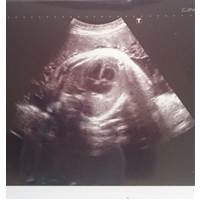

赤ちゃんの心臓が超音波検査で確認できました。心音は「ドッドッ」というリズミカルな速さで確認できました。大人よりも随分と早い鼓動に赤ちゃんの頑張りと力強さを実感します。

37wの妊婦健診では赤ちゃんの骨を確認することができました。臨月にはいって赤ちゃんの胎動が鈍くなりはじめたので成長を目で確認できたのは嬉しかったです。

妊婦健診では背骨を確認しました。妊娠37w頃の赤ちゃんの骨はすべてが硬いわけではありません。産道を通り抜けるために頭蓋骨など柔らかいままの骨もあります。37wの赤ちゃんの頭蓋骨は肩幅と同じくらいの頭囲です。